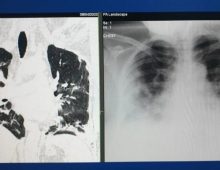

> radiografia pieptului